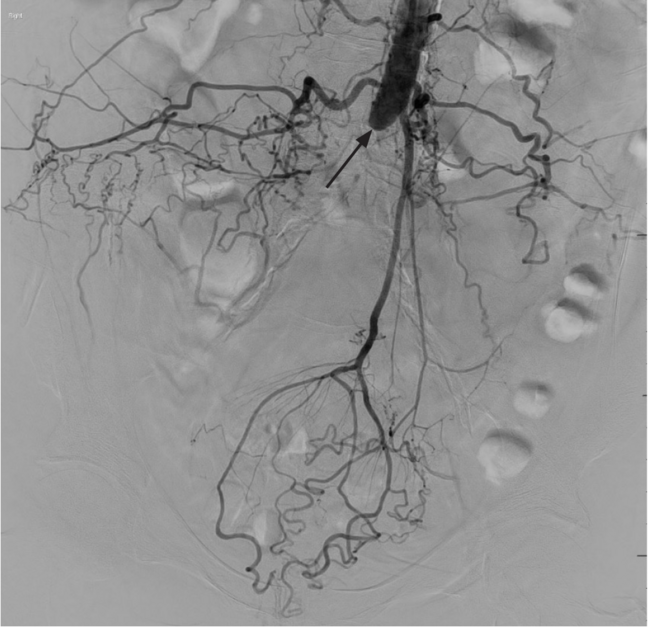

A 62-year-old female with severe lifestyle-limiting claudication and rest pain presented in clinic based on preoperative evaluation with significant inflow disease. Periprocedural brachial aortogram demonstrated extensive abdominal aortoiliac occlusive disease (Figure 1 and Figure 2). The iliac occlusions bilaterally included the common iliac artery (CIA) and left external iliac artery (EIA). Hypertrophied iliolumbar and inferior mesenteric vessels provided collateral circulation. Calcified plaque in the right common femoral artery (CFA) resulted in 85% stenosis.

Using brachial access, right CIA and aortic occlusive disease were successfully recanalized. A wire was passed through the right CFA stenosis. Due to the calcified lesion in the right CFA, Shockwave intravascular lithotripsy (Shockwave Medical) was used in preparation for right groin retrograde access via the profunda femoris artery (Figure 3). The distal aorta, left CIA, and EIA occlusive disease were successfully recanalized.